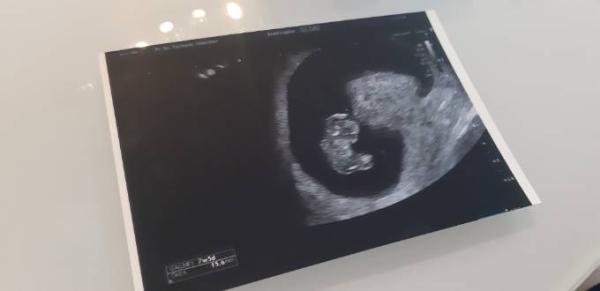

Guten Morgen an alle Januarmamis, auch ich war gestern beim Frauenarzt und durfte unser Krümelchen sehen. Das Herzchen schlägt ganz fest und regelmäßig und es ist mehr als erwartet gewachsen Die Ärztin war sehr zufrieden und hat mir Mut gemacht. Ich wollte das nur mit Euch teilen und wünsche allen ein schönes Wochenende!

Was für ein schönes Bild für die 8. SSW ! Wunderbar